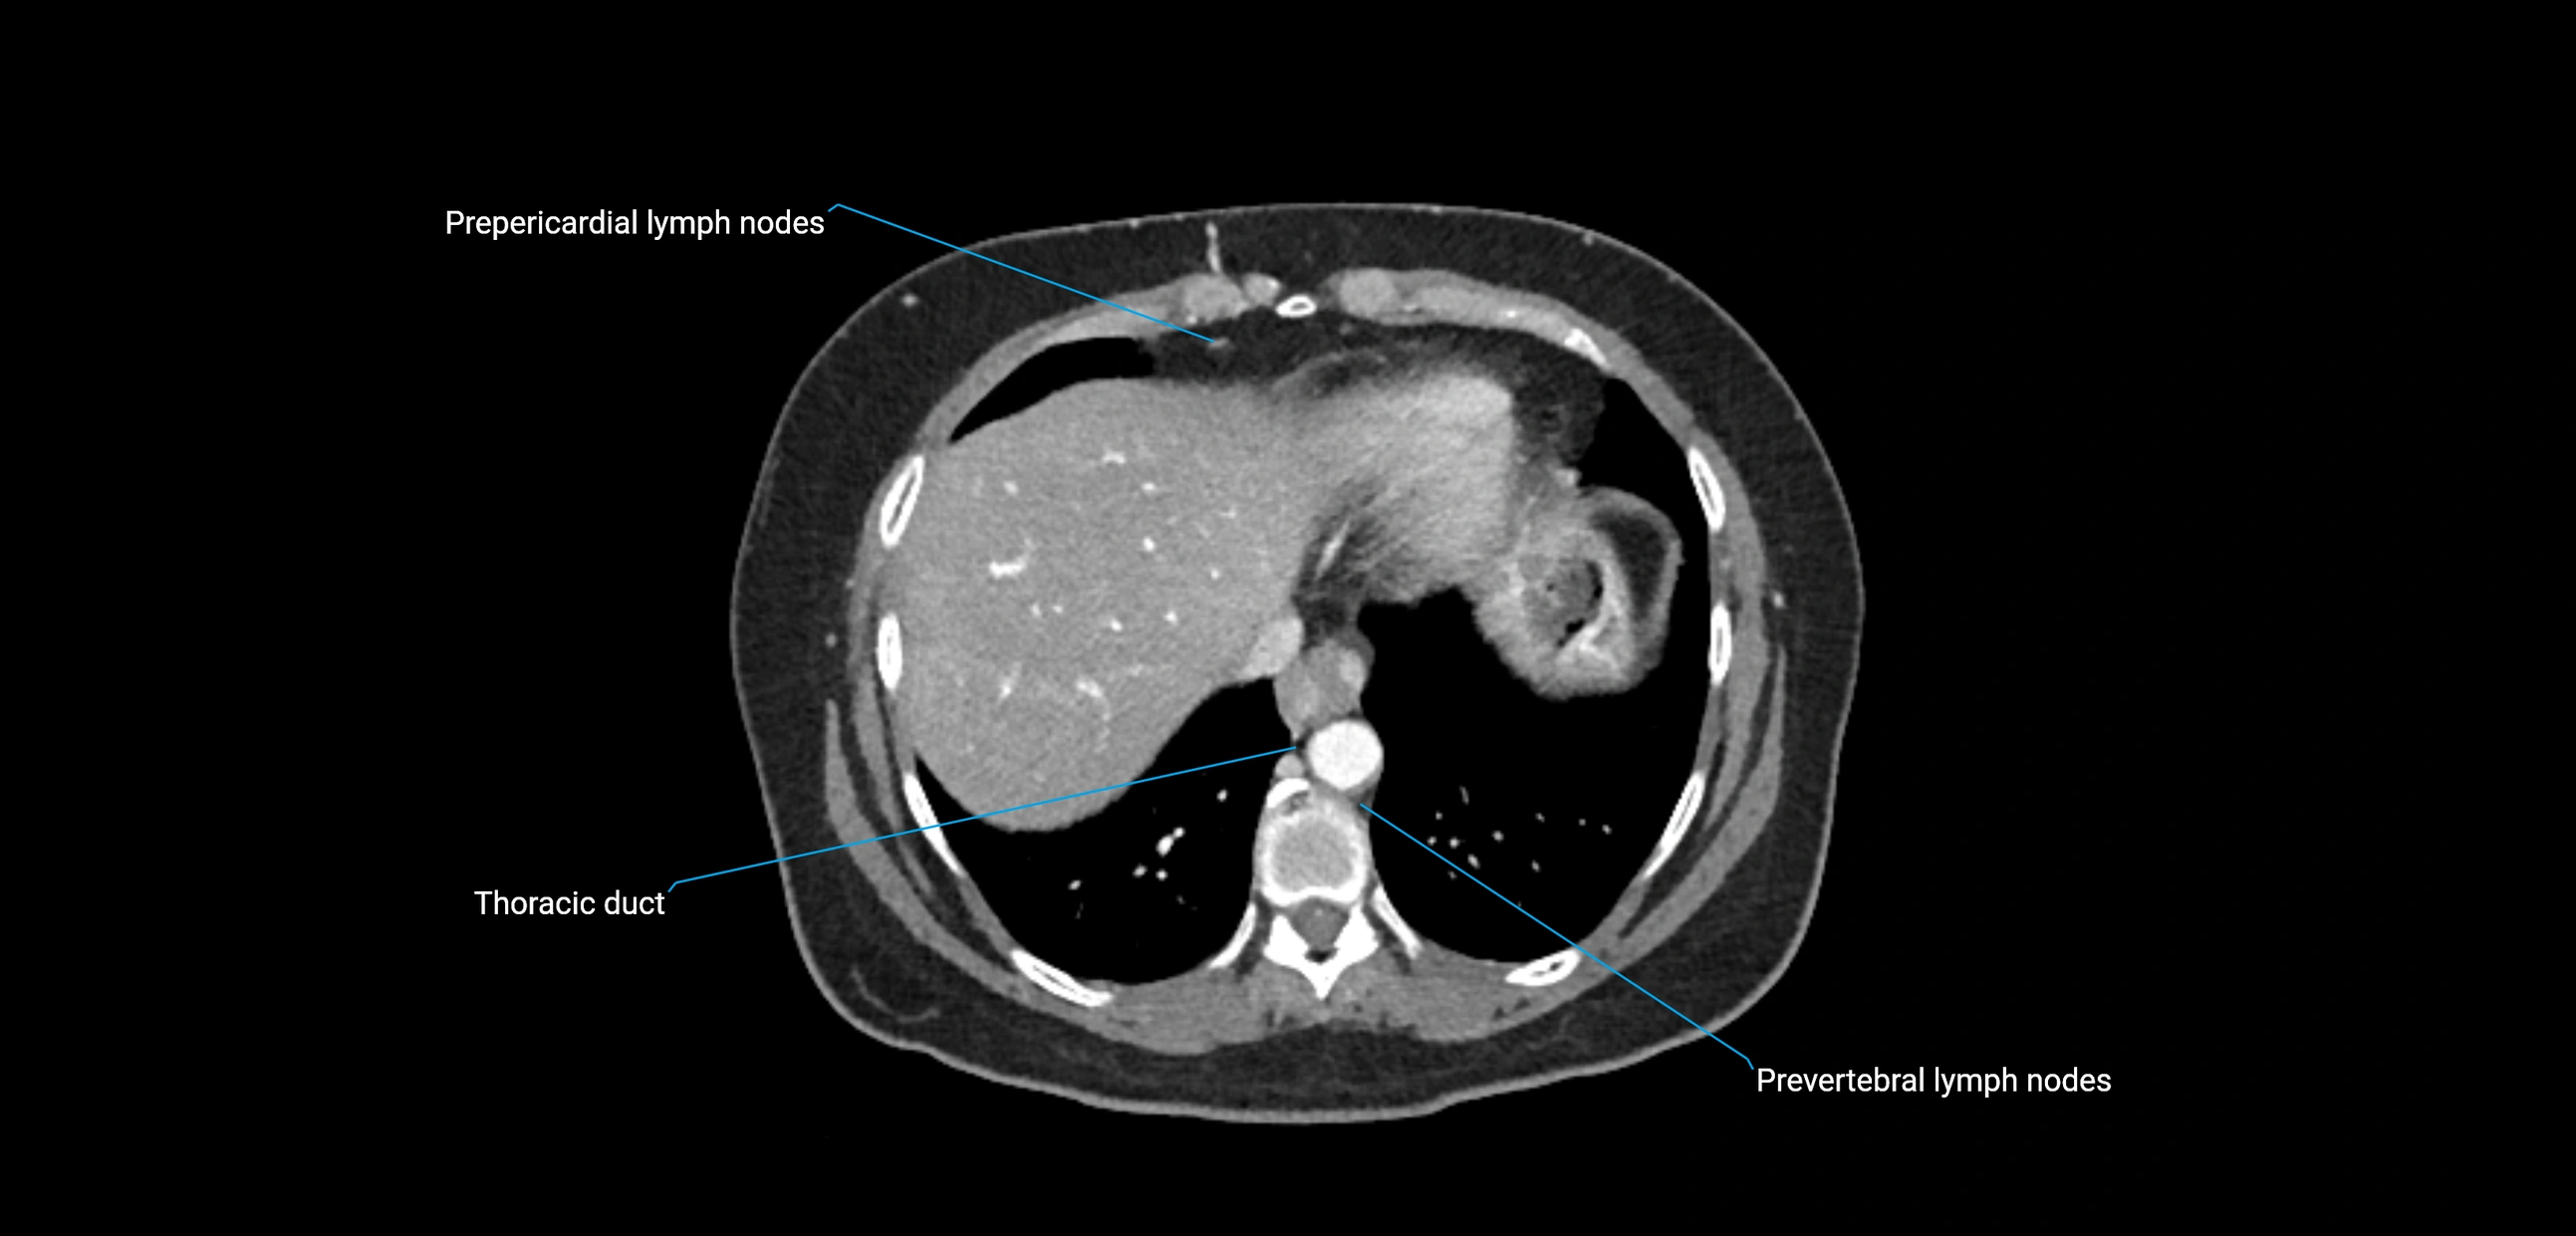

These nodes receive lymph from a wide range of abdominal and pelvic structures. Specifically, they drain lymph from the kidneys, suprarenal glands, gonads (testes/ovaries), uterus, uterine tubes, and pelvic organs, before converging into the lumbar lymphatic trunks, which terminate in the cisterna chyli → thoracic duct.

• Provide a major pathway to the cisterna chyli and thoracic duct

MRI images

image